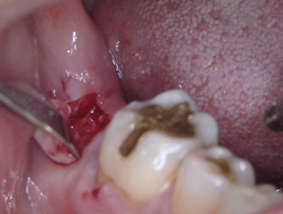

DSC01256.JPG

術前です

右下の一番奥に埋め込みます

DSC01260.JPG

痛そうですが麻酔していますから大丈夫です

歯肉を少し剥がしました

条件が良くて歯肉を剥がさずにできれば

術後の痛みはほとんど痛くありません